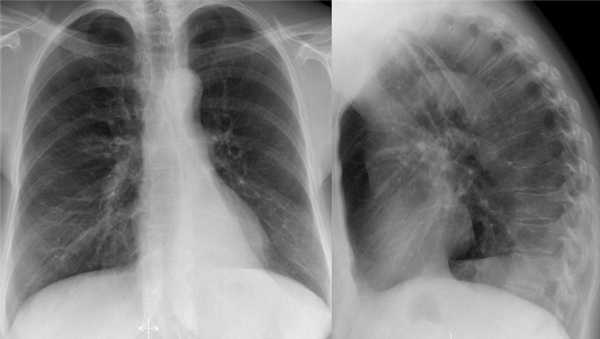

- Минимальное уменьшение объема легкого без подъема левого купола диафрагма.

- В загрудинном пространстве визуализируются изменения высокой плотности, которые спавшейся верхней доли левого легкого.

- Корень левого легкого патологичен, что может соответствовать образованию, обтурирующее просвет бронха.

- Выше перечисленные находки наводят на мысль, что это ателектаз верхней доли левого легкого.

На КТ снимках синей стрелкой указан долевой ателектаз, а красной стрелкой опухоль, которая обтурирует левый верхний долевой бронх (центральный рак легкого.

Ателектаз верхней доли левого легкого с типичным симптомом воздушного серпа (Luftsichel sign — luft(air)+sichel(sickle)), обусловленный гипервентиляцией верхнего сегмента нижней доли левого легкого на фоне коллапса верхний доли левого легкого. Гипервентилируемый

сегмент визуализируется на прямой рентгенограмме от дуги аорты до апикальной части легкого.

- В левом легком патологические изменения высокой плотности с потерей силуэта контуров сердца.

- Высокое стояние диафрагмы левого легкого.

- Смещение вниз косой щели.

- Низкое расположение правого корня легкого.

Данные изменения характерны при тотальном ателектазе верхней доли левого легкого и частичный ателектаз правого легкого. Так контуры сердца справа хорошо визуализируются то, можно сказать, что частичный ателектаз не средней доли, а нижней доли правого легкого.

Оцените нижележащие ПЭТ/КТ изображения. Легочная карцинома обтурирующая левый верхнедолевой бронх и правый верхнедолевой бронх. Множественные метастазы в кости. Стрелкой указан метастаз в ребро.